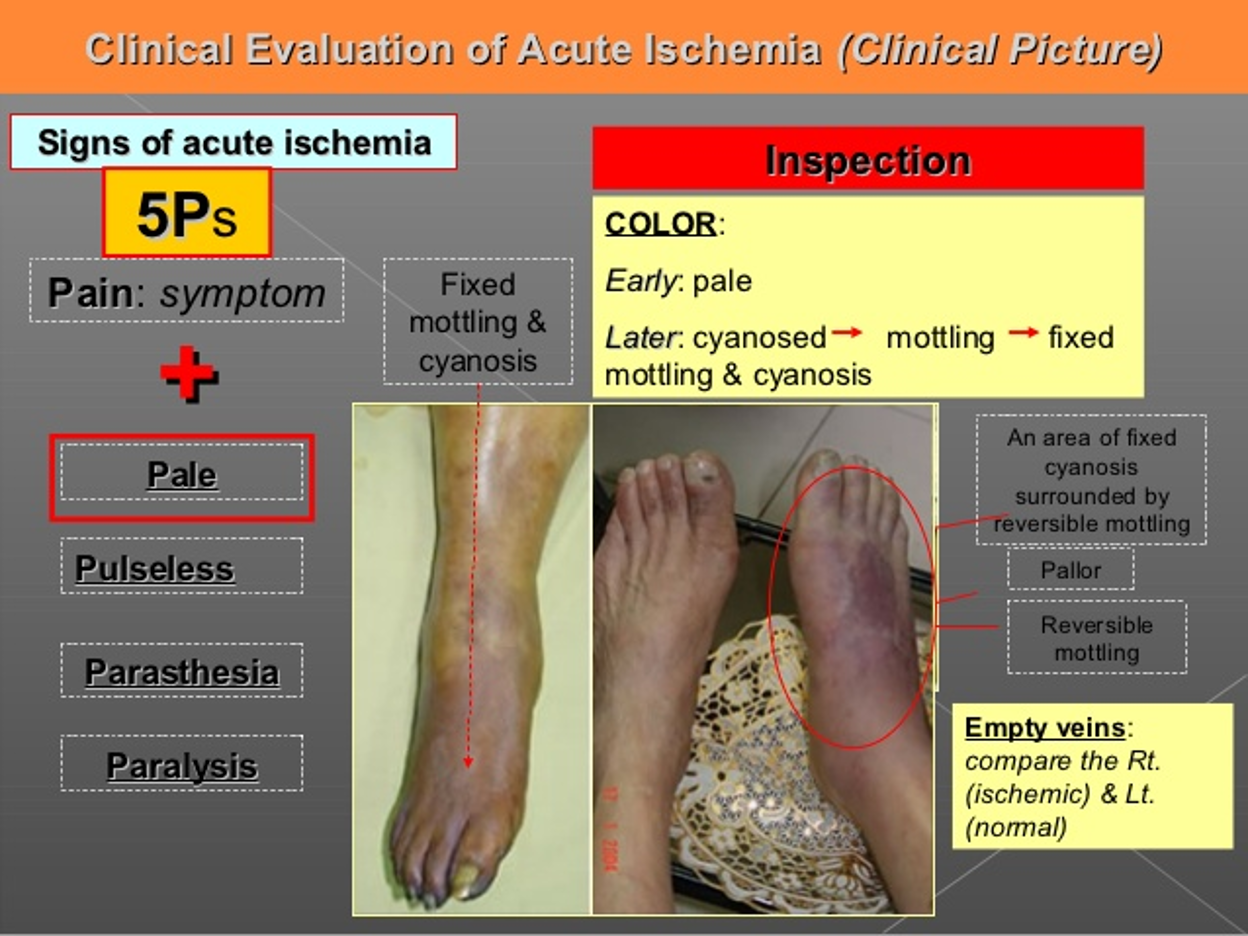

Five “P” of Acute Ischemia

- Pain

- Pallor

- Pulseless

- Paresthesia

- Paralysis

Early: pale

Later: cyanosed ⇒ Mottling

Later stage: Fixed mottling & cyanosis

Early: pale

Later: cyanosed ⇒ Mottling

Later stage: Fixed mottling & cyanosis